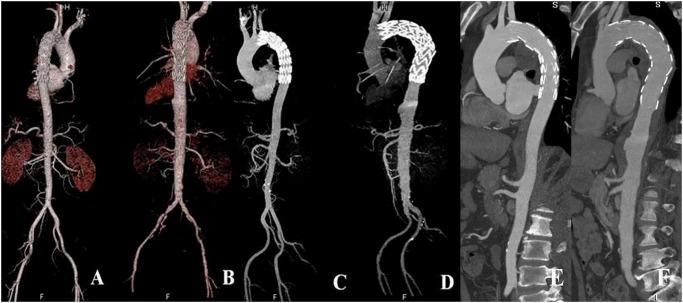

To assess the image quality of aorta obtained by dual-source computed tomography angiography (DSCTA), performed with high pitch, low tube voltage, and low iodine concentration contrast medium (CM) with images reconstructed using iterative reconstruction (IR).

One hundred patients randomly allocated to receive one of two types of CM underwent DSCTA with the electrocardiogram-triggered Flash protocol. In the low-iodine group, 50 patients received CM containing 270 mg I/mL and were scanned at low tube voltage (100 kVp). In the high-iodine CM group, 50 patients received CM containing 370 mg I/mL and were scanned at the tube voltage (120 kVp). The filtered back projection (FBP) algorithm was used for reconstruction in both groups. In addition, the IR algorithm was used in the low-iodine group. Image quality of the aorta was analyzed subjectively by a 3-point grading scale and objectively by measuring the CT attenuation in terms of the signal- and contrast-to-noise ratios (SNR and CNR, respectively). Radiation and CM doses were compared.

The CT attenuation, subjective image quality assessment, SNR, and CNR of various aortic regions of interest did not differ significantly between two groups. In the low-iodine group, images reconstructed by FBP and IR demonstrated significant differences in image noise, SNR, and CNR (p<0.05). The low-iodine group resulted in 34.3% less radiation (4.4 ± 0.5 mSv) than the high-iodine group (6.7 ± 0.6 mSv), and 27.3% less iodine weight (20.36 ± 2.65 g) than the high-iodine group (28 ± 1.98 g). Observers exhibited excellent agreement on the aortic image quality scores (κ = 0.904).

CT images of aorta could be obtained within 2 s by using a DSCT Flash protocol with low tube voltage, IR, and low-iodine-concentration CM. Appropriate contrast enhancement was achieved while maintaining good image quality and decreasing the radiation and iodine doses.